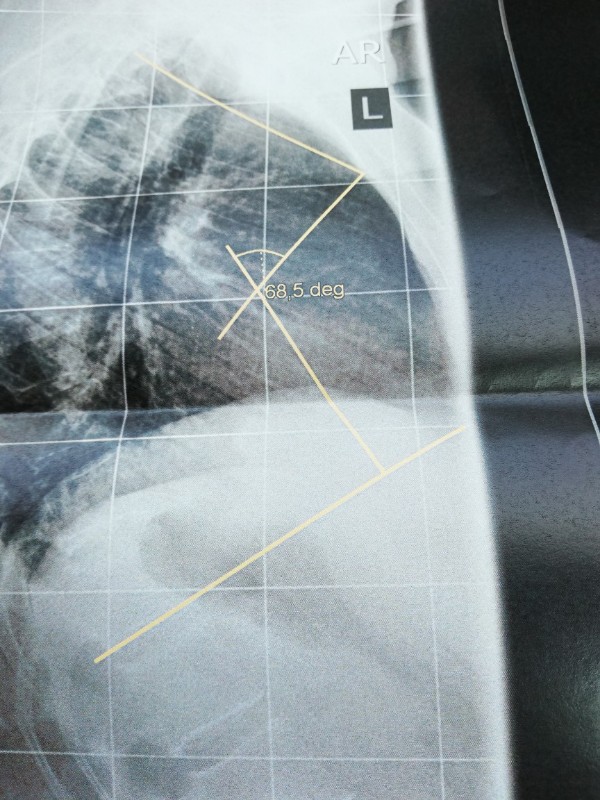

- IMG_20190329_114551-864x1152-600x800.jpg (127.7 KiB) 8584 mal betrachtet

- IMG_20190329_114843-864x1152-600x800.jpg (101.8 KiB) 8584 mal betrachtet

Nachdem ich gestern bei Dr. AL Alwan in Bottrop war, bin ich heute direkt in Oberhausen zum Röntgen der seitlichen Wirbelsäule gefahren. Dr. Al Alwan ist der Ansicht meine Beschwerden könnten von einer Kyphose kommen. Ich bin 54 Jahre alt und habe seit ca 2 Jahren teilweise unerträgliche Schmerzen. Meine Hausärztin ist der Meinung die Schmerzen sind somatoform und mein bisheriger Orthopäde löst mir regelmäßig Blockaden und rät mir zu Sport und Yoga. Leider werden die Schmerzen dadurch schlimmer. Ein MRT 2018 ergab eine leichte Skoliose und eine leichte Kyphose. Leider konnte ich heute mit keinem Arzt über das Röntgenbild sprechen. Es sind Winkel mit 68,5 deg eingezeichnet. Sagt das jemanden was? Es steht nichts von Cobb o. ä. dabei. Ich bin ziemlich ratlos ob das die Ursache der Schmerzen sein könnte. Freue mich über jede Erfahrung oder Tipp von euch. Falls es klappt lade ich mal 2 Bilder hoch. LG und ein schönes, sonniges Wochenende

68,5 Grad könnte sich auf die Hyperkpyhose beziehen, eine normale BWS Kyphose liegt im Bereich 25-40 Grad.

Dr. AL Alwan war nach der Untersuchung der Meinung, dass die Skoliose nicht sonderlich ausgeprägt wäre und mein Rücken sichtbar rund sei. Deshalb die Überweisung zum Röntgen um die Kyphose zu vermessen. Allerdings wurde nur eine seitliche Aufnahme der gesamten Wirbelsäule gemacht. Den Ausdruck und eine CD vom BWS - MRT von 2018 habe ich in seinen Briefkasten geworfen, ich denke nächste Woche weiß ich mehr. Mir ist nur nicht klar ob die 68,5 ged mit Cobb gleichzusetzen sind